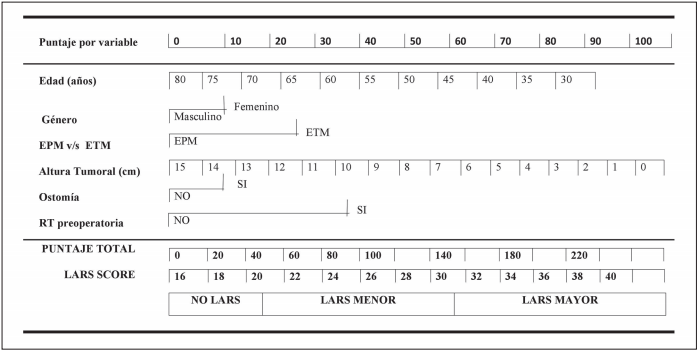

Mauricio Andres Zambra Rojas, Günther Ronny Bocic alvarez, Mario Antonio Abedrapo Moreira, Antonella Sanguinetti Montalva, Jose Luis Llanos Bravo, Rodrigo Azolas Marcos, Mauricio Javier Diaz Beneventi, Tomas Rodriguez Castillo, Natalia Moreno Baeza, Felipe Bocic W

|

|

|

Günther Ronny Bocic Alvarez, Mauricio Andres Zambra Rojas, Mario Antonio Abedrapo Moreira, Antonella Sanguinetti Montalva, Jose Luis Llanos Bravo, Rodrigo Azolas Marcos, Mauricio Javier Diaz Beneventi, Felipe Ignacio Bocic Wattier, Tomas Rodriguez Castillo, Natalia Moreno Baeza

|

|

|